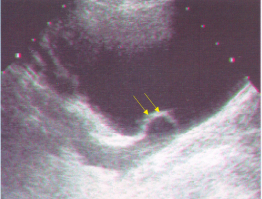

62 附圖中箭號所指的解剖結構為:

(A)左門靜脈主要分支(left main branch) (B)右門靜脈主要分支(right main branch)(C)門靜脈第三節段分支(segment-3 branch) (D)門靜脈第二節段分支(segment-2 branch)